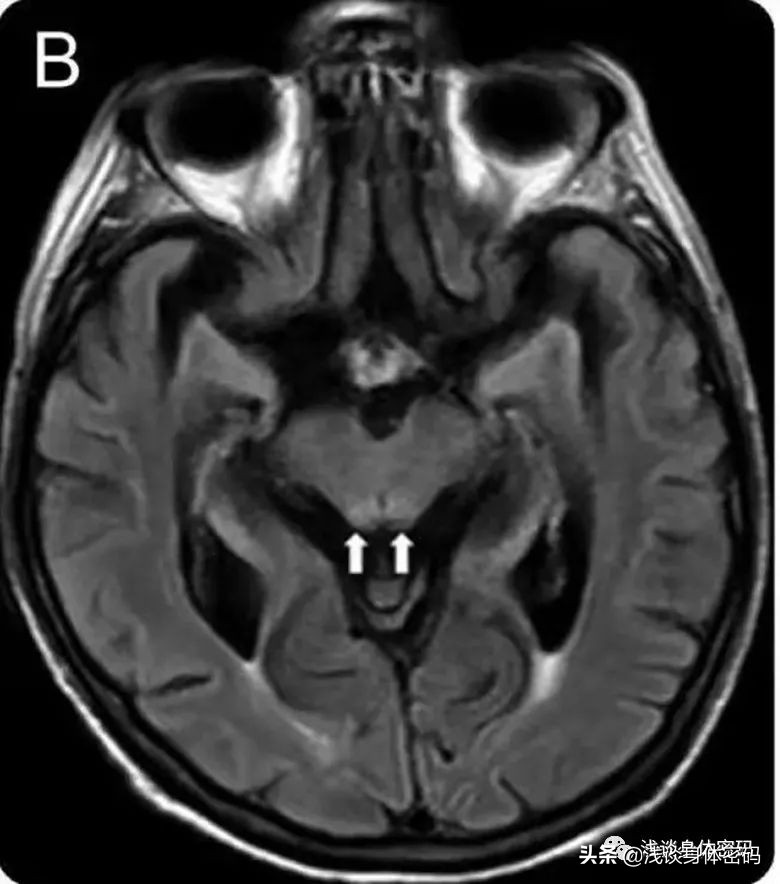

MIE的首选检查方法是头颅MRI,通常显示小脑齿状核附近区域特有的对称性病变,亦可累及胼胝体压部、脑桥被盖部、中脑、脑白质、基底节区等。齿状核对称性病变常用来区分其他原因引起的脑病。

MRI Flair显示双侧小脑齿状核、上丘和导水管周围灰质对称性高信号: